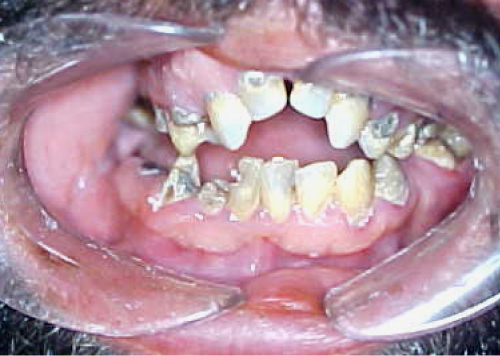

A thirty-seven-year-old male patient presented to the Oral and Maxillofacial Clinic of "Evangelismos" Hospital complaining of the inability to open his mouth since his birth. When the medical history was received, it was found that the unilateral TMJ ankylosis was of congenital etiology due to the operative instrumental delivery. The patient had undergone corrective surgery before years, but the ankylosis had relapsed. During the clinical examination the maximum opening of the mouth was 2-3 mm, while the lateral movements of the mandible were depressed. The development of the anterior region of the maxilla was disturbed and formed in a V-shaped dental arch due to the use of a feeding instrument from neonatal age (Figure 1). Α conventional radiographic examination was performed including a panoramic X-ray, as well as a CT and three-dimensional CT scan. Radiological examinations showed that the ankylosis was in the right TMJ due to the development of bone between the condyle and the articular fossa including anterior and posterior articular tubercle (Figure 2).

Figure 1: Limited opening of the mouth and the V-shaped formation of the maxilla. View Figure 1